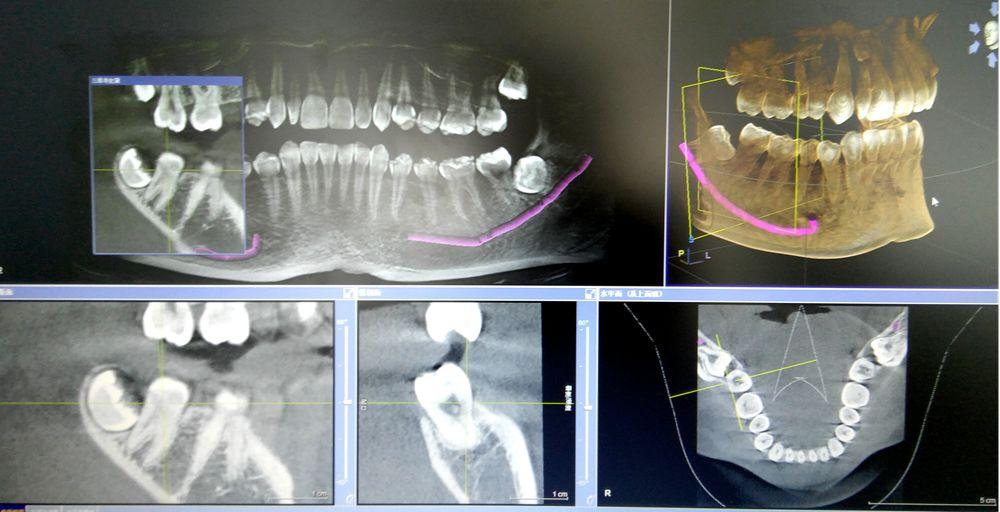

我院口腔科配備的西諾德口腔CBCT(錐形束CT),在業(yè)界被譽為神奇的“慧眼”,它能夠幫助口腔醫(yī)生詳細,清晰,了解患者口腔內(nèi)部的情況,是世界牙科聯(lián)盟指定的品牌儀器,具有當前世界先進的技術(shù)優(yōu)勢。

1.采集的信息量更多,采用錐形束360°容積掃描方式。

2.掃描范圍更大,掃描時間更短。

3.輻射劑量更低,一次CT拍攝只有29uSv,僅為普通CT的幾十分之一。

4.更高空間分辨率,對于頜面部骨骼和牙齒等硬組織的顯示比普通CT清晰約10倍。

5.影像后期處理功能強大,可以任意層厚、任意層距、任意切面,多方位、多角度的觀察病變。

6.適用范圍更廣、診斷更加,牙齒種植術(shù)前骨量及密度分析,埋伏牙的定位,牙齒矯正前的頭顱測量,復雜的根尖周病變的診斷,阻生齒拔除方案的詳細制定,頜骨囊腫范圍的確定,顳下頜關(guān)節(jié)骨質(zhì)的檢查等。

CBCT掃描可準確分析頜骨植入?yún)^(qū)的骨質(zhì)、骨量、骨密度及植體與下頜神經(jīng)管、上頜竇的關(guān)系,臨床醫(yī)生可以在圖像上模擬種植,直接與患者進行溝通及交流,并可指導手術(shù)者在手術(shù)方案中避開危險區(qū)域,手術(shù)的性。此外,臨床醫(yī)生還可以利用CT數(shù)據(jù)進行數(shù)字模型重建,配合軟件預先做好手術(shù)模板使種植手術(shù)更快捷。

牙槽外科及頜面外科

通過CBCT可以觀察阻生牙、埋伏牙的牙根彎曲情況及與上頜竇、鼻底、下牙槽神經(jīng)管、頦孔等重要解剖結(jié)構(gòu)的關(guān)系,方便醫(yī)生拔牙前的術(shù)前評估。也可以觀察頜骨囊腫等病變在三維空間中的范圍,了解病變與上頜竇、神經(jīng)管等重要解剖結(jié)構(gòu)的關(guān)系,提高手術(shù)。